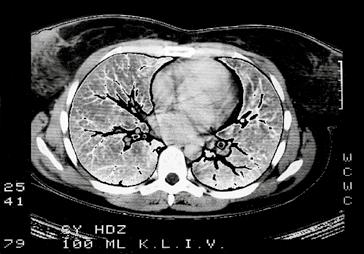

Kromě nakladatelství a výtvarníka se o definitivní podobu třetího dílu učebnice zasloužili mnozí odborníci. Za poskytnutí rtg snímků jsem již od vzniku 1. vydání 3. dílu učebnice vděčný Radiodiagnostické klinice 1. LF UK a paní doc. MUDr. Běle Drugové, DrSc., z radiodiagnostického oddělení Nemocnice Na Homolce. Za vynikající mikrofotografie z vývoje oka děkuji panu prof. MUDr. Františku Vrabcovi, DrSc., který mi je poskytl pro tuto knihu. Panu prof. MUDr. Oldřichu Eliškovi, DrSc., a paní doc. MUDr. Miloslavě Eliškové, CSc., děkuji za poskytnutí podkladů z jejich studií pro vytvoření obrazů mízního odtoku ze srdce. Panu doc. MUDr. Jaromíru Hradcovi, CSc., ze III. interní kliniky 1. LF UK děkuji za poskytnutí echokardiografických obrazů srdce. Upřímně děkuji též oběma spolupracovníkům, panu prof. MUDr. Rastislavu Drugovi, DrSc., a panu prof. MUDr. Miloši Grimovi, DrSc., za porozumění a sympatickou spolupráci na tomto vydání knihy. Studentům, učitelům anatomie i lékařům přeji, aby jim kniha sloužila jako užitečný průvodce a pomocník při studiu tohoto náročného oboru.